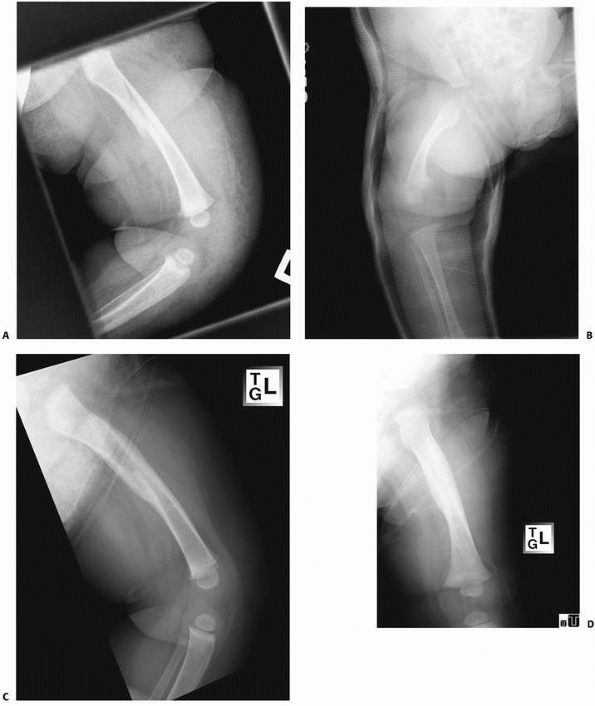

![]() |

FIGURE 22-4 A. This 7-month-old sustained a low-energy spiral femoral shaft fracture. B. Treatment was in a spica cast. C,D. Excellent healing with abundant callus at only 4 weeks after injury.